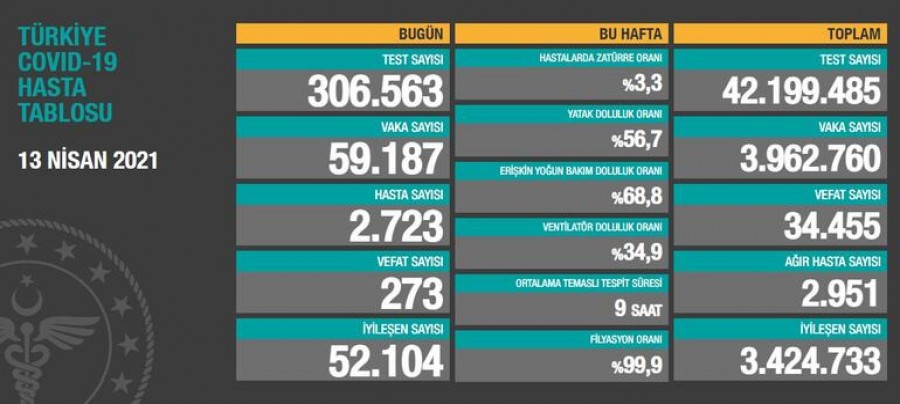

24 saatte 59.187 yeni vaka!

Sağlık Bakanlığı’nın internet sitesinde yer alan “Türkiye Günlük Koronavirüs Tablosu” güncellendi. Türkiye’de son 24 saatte 306 bin 563 Kovid-19 testi yapıldı, 59 bin 187 kişinin testi pozitif çıktı, 273 kişi hayatını kaybetti.

Sağlık Bakanlığı’nın “Türkiye Günlük Koronavirüs Tablosu“nda Türkiye’nin güncel korona virüs tablosu kamuoyuyla paylaşıldı.

Türkiye’de son 24 saatte 306 bin 563 Kovid-19 testi yapıldı, 59 bin 187 kişinin testi pozitif çıktı, 273 kişi hayatını kaybetti.

Ağır hasta 2 bin 951 oldu, 52 bin 104 kişinin Kovid-19 tedavisinin/karantinasının sona ermesiyle iyileşen sayısı 3 milyon 424 bin 733’e yükseldi.